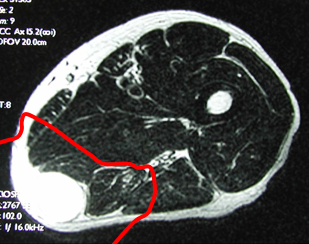

骨表面の膜(骨膜),軟骨,筋表面の膜(筋膜)などを腫瘍の浸潤を防ぐ組織(バリアー)と見なし,このバリアーで腫瘍を包むように切除する手術です(治癒的切除)。バリアーの無い部位では腫瘍からできるだけ離し正常組織(腫瘍辺縁からの距離を計算;○cm)を含めて切除します(○cm広範切除)。安全な切除縁で腫瘍を切除することが重要であり,術後再発率はほぼ5%程度になります。当科では,MRIやCT像を基にバリアーの存在を診断し綿密に手術計画を立て,3cm以上の広範切除獲得を基本としています。

軟部肉腫症例 広範切除